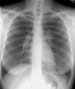

Löfgren syndrome is classically described as a triad of EN, polyarthritis, and hilar adenopathy. The adenopathy may be unilateral or bilateral hilar and/or right paratracheal lymphadenopathy. Other symptoms include anterior uveitis, fever, ankle periarthritis, arthralgias, and pulmonary involvement.

Löfgren syndrome is usually an acute disease with an excellent prognosis, typically resolving spontaneously from 6-8 weeks to up to 2 years after onset. Pulmonologists, ophthalmologists, and rheumatologists often define this syndrome differently, describing varying combinations of arthritis, arthralgia, uveitis, EN, hilar adenopathy, and/or other clinical findings. (See the image below.)

Bilateral hilar lymphadenopathy.